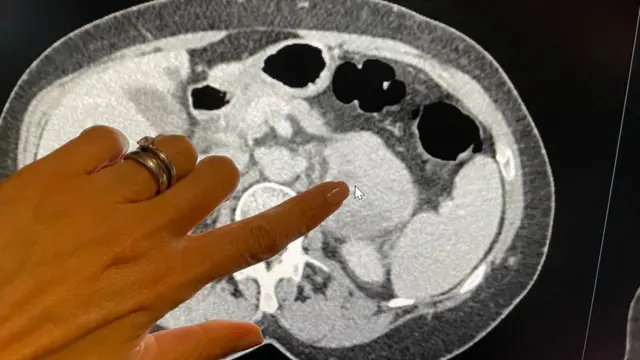

محققان در نشریه لنست انکولوژی نوشتهاند که در اسکن ۱۷۰ بیمار از تکنیکی به نام رادیومیک برای شناسایی علائم غیرقابل مشاهده «سارکوم خلفی صفاقی» که در بافت همبند پشت شکم ایجاد میشود، استفاده کردهاند.

با این دادهها، الگوریتم هوش مصنوعی توانست تهاجمی بودن ۸۹ تومور دیگر بیماران در بیمارستانهای اروپا و آمریکا را از طریق اسکن، بسیار دقیقتر از نمونه برداری که در آن تنها بخش کوچکی از بافت سرطانی زیر میکروسکوپ تجزیه و تحلیل می شود، درجه بندی کند.

وقتی تینا مک لاگلان، پرستار دندانپزشکی، در ژوئن سال گذشته، پس از درد معده با سارکوم در پشت شکمش تشخیص داده شد، پزشکان برای یافتن این مشکل به تصاویر اسکن توموگرافی کامپیوتری (CT) تکیه کردند.